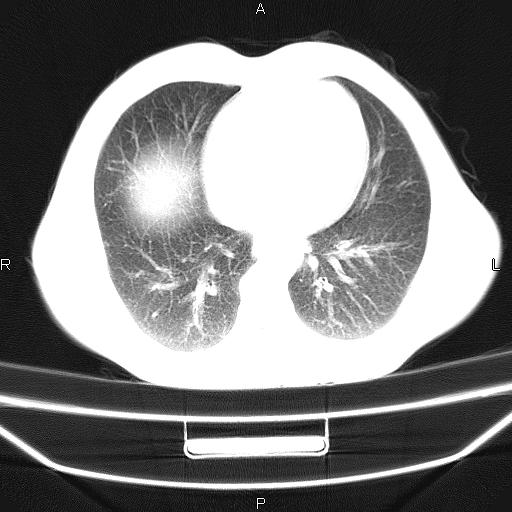

患者,男,40岁。间断发热,咳嗽二十余日。体温最高达38.9° 在当地诊所抗炎治疗三天后体温降至正常,患者自行停药。今又发热。胸片示,左下肺阴影。

左下肺片状高密度影,境界模糊,密度不均,考虑感染性病变可能性大,建议抗炎治疗后复查。左肺门增大,不除外占位性病变,必要时支气管镜检。